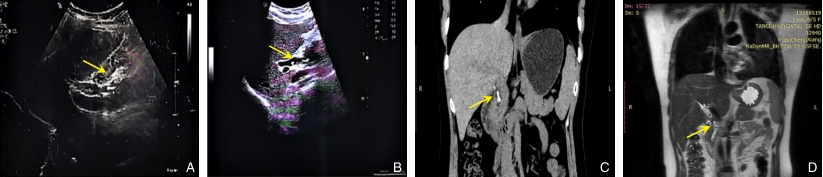

图3 患者术后随访影像学检查 A:术后胸腹部CT平扫图像,清晰显示胆总管内T管位置;B-D:术后2个月经T管窦道行胆道造影图像(不同体位/角度),显示造影剂充盈良好,肝内外胆管显影清晰、通畅,未见充盈缺损(结石或异物残留),十二指肠顺利显影Fig.3 Postoperative follow-up imaging A: Plain CT scan showing the position of the T-tube in the common bile duct; B-D: T-tube cholangiography via the sinus tract at 2 months postoperatively (different positions/angles), demonstrating good contrast filling, patent intrahepatic and extrahepatic bile ducts, no filling defects, and smooth passage into the duodenum